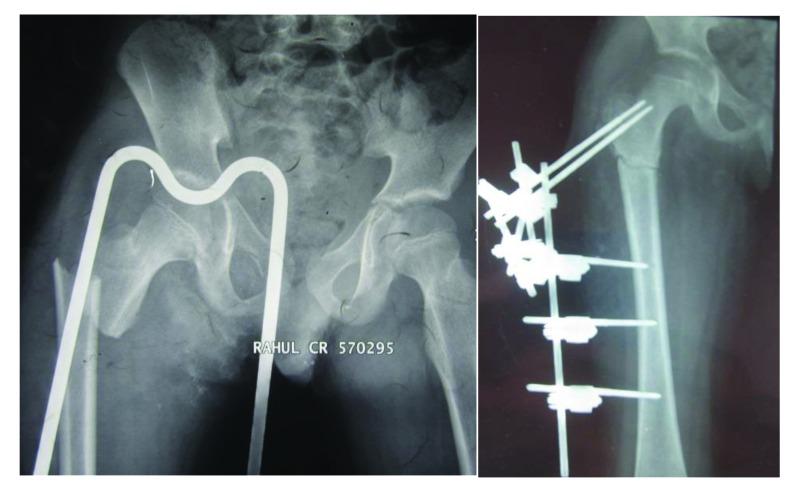

小儿股骨干骨折的当前概念

Current Concepts in Paediatric Femoral Shaft Fractures.

Pediatric femoral shaft fractures account for less than 2% of all fractures in children. However, these are the most common pediatric fractures necessitating hospitalization and are associated with prolonged hospital stay, prolonged immobilization and impose a significant burden on the healthcare system as well as caregivers. In this paper, the authors present a comprehensive review of epidemiology, aetiology, classification and managemement options of pediatric femoral shaft fractures.

摘要